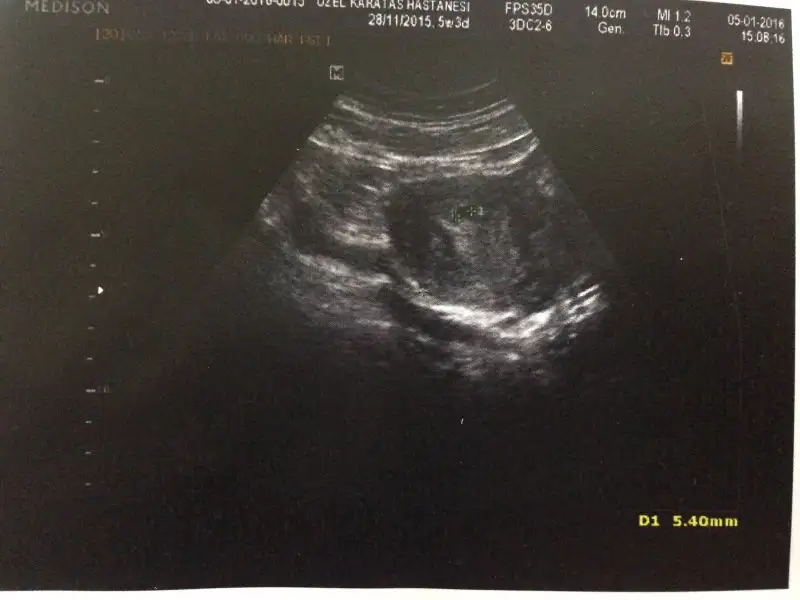

6+3 hafta kese boş

image.webp